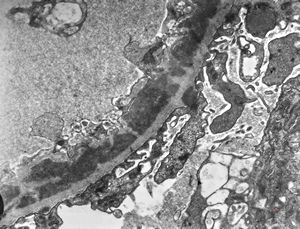

M,6y. | Alport syndrome- digital photo from the screen